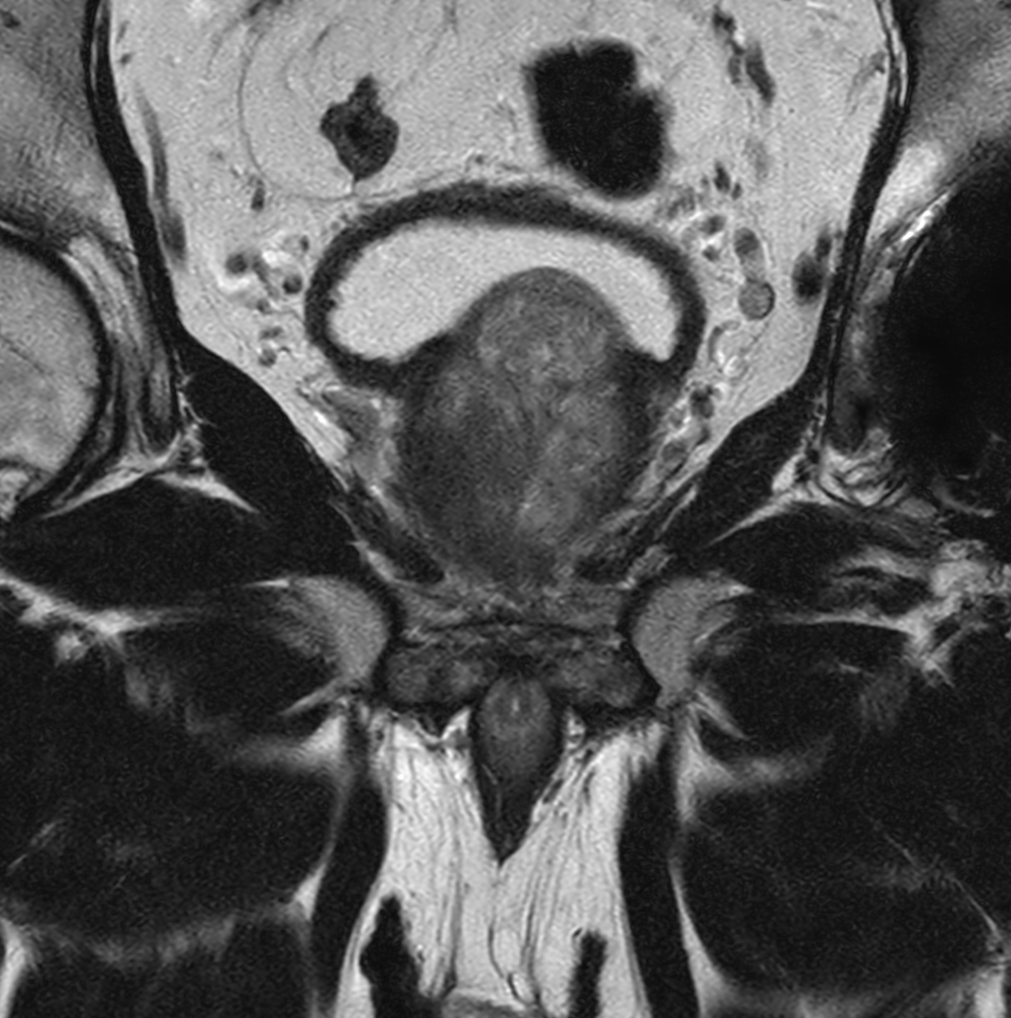

Coronal T2w TSE